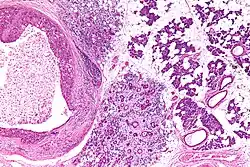

Their histologic appearance is similar to ductal breast carcinoma.

Intermed. mag.